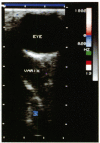

Colour Doppler imaging (CDI) is a recent development in ultrasonography. It allows simultaneous two-dimensional structural imaging and Doppler evaluation of blood flow. Quantitative information on flow velocity is obtained by pulsed Doppler spectral analysis, the colour information being used to choose the vessel of interest. Using this technique the authors examined a patient with an orbital varix previously diagnosed by clinical findings and computed tomography. Dynamic evaluation with real-time direct imaging of flow facilitated the diagnosis of this orbital disorder without the need for any contrast material. This technique may prove to be a useful adjunct to computed tomography for the evaluation of suspected vascular lesions of the orbit.